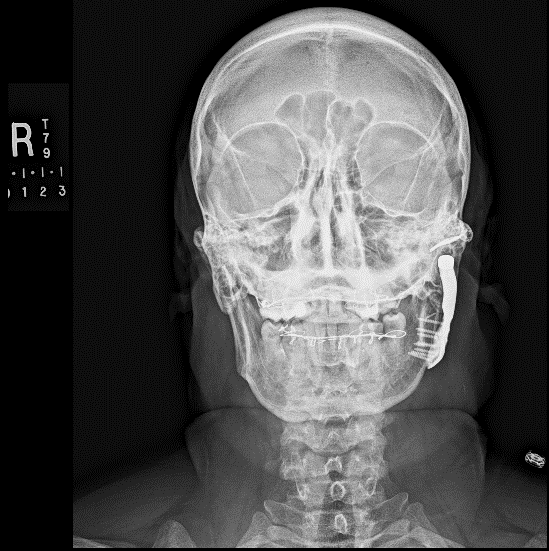

Joint replacement is a significant operation for symptomatic irreparably damaged joints. Costochondral rib graft (see Figure 7) or customised prosthetic joints are used. The unpredictability of costochondral rib (a third are stable, a third resorb and a third overgrow) and refinements to customised prostheses have moved almost all jaw joint replacement for terminal joint damage to these devices (see Figure 8).

Figure 7: Postoperative X-ray radiograph of a costochondral rib graft total condyle replacement.